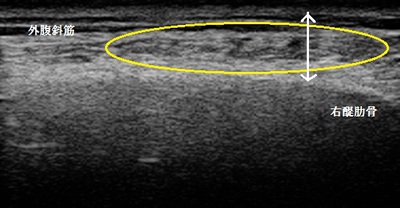

左第三腰椎超音波短軸像 右同部

腰を屈めてやっと歩ける状態でした。超音波検査を行ったところ左腰部起立筋群が損傷して内出血や

浮腫を起こして腫れている様子が認められました(上画像線で囲んだ黒い個所)。